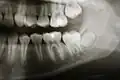

Jest to zdjęcie przeglądowe przedstawiające ogólny stan wszystkich zębów, zawiązków zębów oraz struktur je otaczających takich jak kości szczęki i żuchwy, stawy skroniowo-żuchwowe i częściowo zatoki szczękowe, jest również pomocne w ocenie wad rozwojowych[1], urazach i nowotworach.

Za pomocą pantomogramu można wykryć wiele nieprawidłowości, jak np. próchnica, zmiany okołowierzchołkowe, zęby zatrzymane, dodatkowe i nadliczbowe, zęby nieprawidłowo przeleczone kanałowo. Ze względu jednak na ogólny obraz czasami wymagane jest wykonanie dodatkowo dokładniejszego zdjęcia zębowego podejrzanej okolicy. Pantomogram daje również pogląd na stan kośćca w przypadku planowania zabiegu wszczepiania implantów zębowych – jednak w tym wypadku najczęściej korzysta się z tomografii komputerowej.

Pantomogram nie odzwierciedla rzeczywistych rozmiarów obrazowanych tkanek – szczęki i trzon żuchwy są wydłużone, gałęzie żuchwy skrócone[1], a obraz jest średnio powiększony o 15%.

Pantomogram jest zdjęciem warstwowym[11], co powoduje, że niektóre struktury mogą nie być uwidocznione na zdjęciu, jeśli nie znajdowały się w okolicy warstwy badanej przez pantomograf. Przykładem może być kanał żuchwy, a także zatoka szczękowa, której zachyłek zębodołowy widać na zdjęciu, ale nie przebieg całego jej dna. Wady tej nie posiadają zdjęcia sumacyjne i tomografia komputerowa.

Oprócz tego na zdjęciu nakładają się struktury – przykładowo kręgosłup szyjny nakłada się w okolicy siekaczy oraz powierzchnie styczne zębów nakładają się na siebie, szczególnie w odcinkach bocznych[11][2].